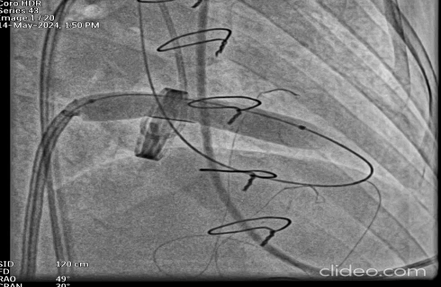

Fluoroscopy Revealed Stuck Prosthetic leaflets. She was planned for emergency percutaneous management in view of her present clinical and lab fincdings

Cerebral Protection was done with one filter and two peripheral balloons

Transeptal Puncture was done and was later exchanged with 8.5fr deflectable Agilis sheath

Bilateral Radial and Femoral artery access taken along with Right Femoral vein under Ultrasound guidanceCarotid filter was placed in Right carotid artery through Right femoral arteryTwo Peripheral balloons were kept in left common carotid and left subclavian through left femoral and radial artery routeTranseptal puncture through right femoral vein was done and was later exchanged with 8.5fr deflectable Agilis sheathThrough Agilis sheath valve orifices was crossed with 0.032 Terumo wireUpper Orifice was dilated with 12x140mm peripheral balloonCentral Orifice was dilated with 5x60mm peripheral balloonLower Orifice was dilated with 10x140mm peripheral balloonPost Procedure Good movement of both leaflets , still upper leaflet movement was not satisfactory.6fr Decapolar mapping catheter was used for pecking the upper leaflet and later again it was dilated with 12x140mm peripheral balloon.Movement of both leaflets were good